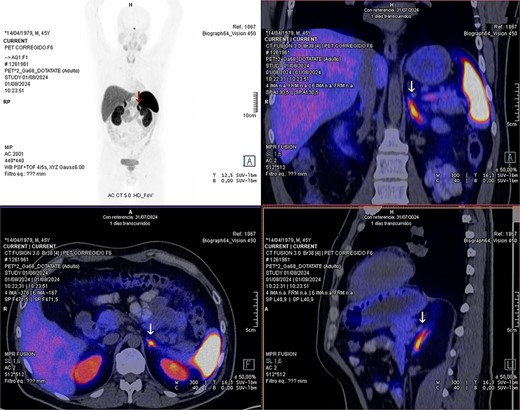

Laboratory studies were complemented with elevated metanephrines in urine three times the normal value (3.19 mg/24 hours), and in a gadotatate positron emission tomography (PET-SCAN) study (Fig. 1), showed a slightly enlarged left adrenal gland with increased metabolic activity, leading to the diagnosis of left pheochromocytoma.

PET-SCAN with gadotatate study with the tumor capitation evidence (arrows).